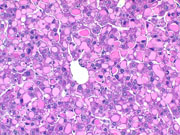

Hyaline bodies are occasionally seen in liver degeneration as well as in hepatocellular neoplasms of mice. In this example a large number of large hyaline bodies are concentrated in one region of the liver.